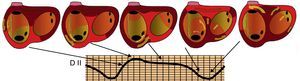

Figura 4. Cartografía electroanatómica (Navx®) de taquicardia auricular focal originada en la aurícula izquierda paraseptal. La imagen del torso indica la posición de las vistas (anterior a la izquierda, posterior con angulación caudal a la derecha). La escala de tiempo, a la izquierda, marca blanco el inicio de activación y violeta el final. Obsérvese la propagación centrífuga uniforme (blanco → amarillo → verde → azul → violeta) que converge en la aurícula izquierda posterior.